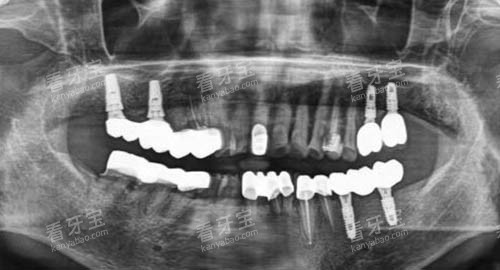

通过较高的口腔检查设备,如口腔 CT、全景片机等,能够较准地获取患者口腔的详细信息。

在种植牙方面,医生们掌握了较高的种植技术,能够熟练地进行各种种植手术,确保种植体的稳定性和成功概率。

安徽芜湖中诺口腔引进了一系列国内外较高的口腔诊疗设备,如智能化口腔综合治疗台、激光治疗仪、超声洁牙机等。

例如,智能化口腔综合治疗台可以实现口腔影像的实时采集和分析,医生可以通过电脑屏幕清晰地观察患者口腔内部的情况,为诊断和治疗提供较准的依据。